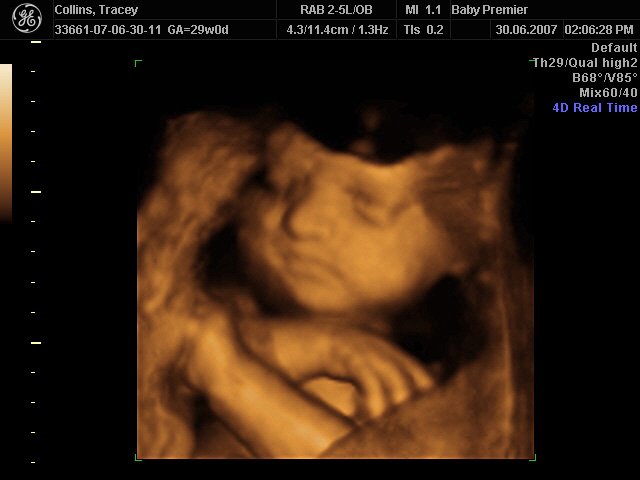

On 30th June 2007, we had a scan of our baby done in "4D" - fancy speak for a moving 3D image.

So sit back, relax, and enjoy Baby O in glorious 4D!